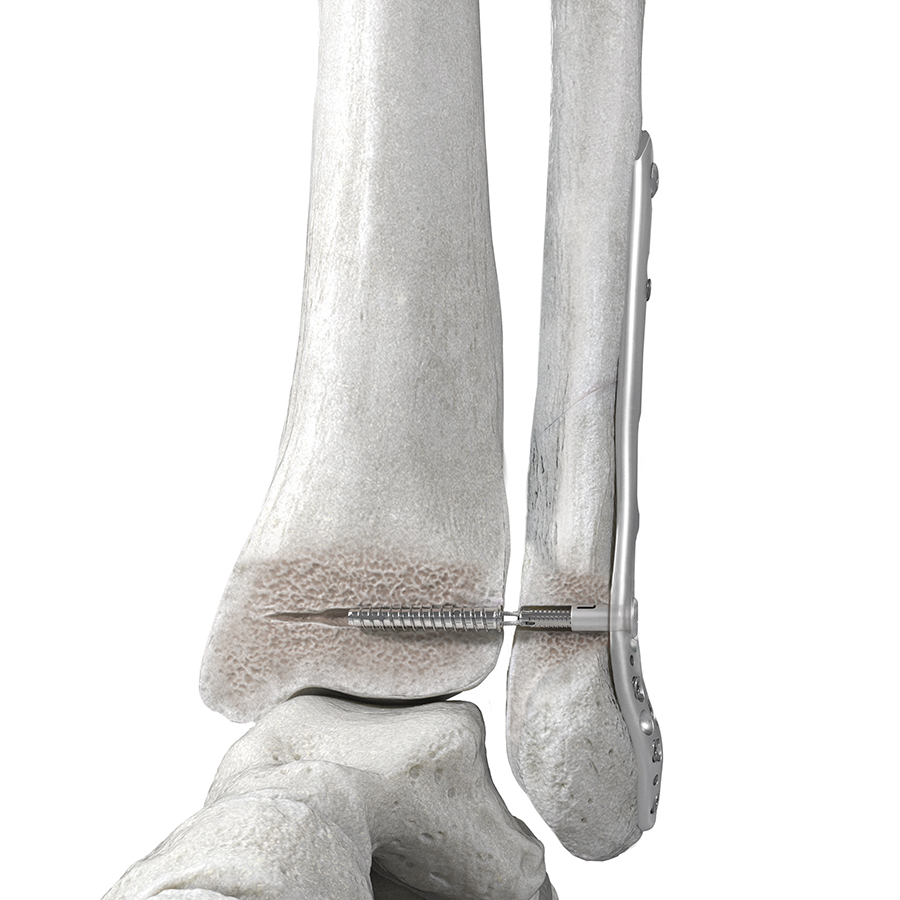

The FIBULINK™ Syndesmosis Repair System (Fig 1) combines the benefits of fixation of a screw and the flexibility of a suture. A short, high-strength suture bridge helps to restore the physiologic ankle motion.

The implant is a multicomponent anchor system consisting of four main components (Fig 1):

- Fibula Tensioning Cap: interfaces with the Fibula Link. A rotation of the Tensioning Cap applies tension to the construct.

- Fibula Link: transfers the tension applied by the Fibula Tensioning Cap to the Suture Bridge. As such, it functions as an interface in the primary tension mechanism.

- Suture Bridge: applies compression between the fibula and the tibia via transferring the tension between the Fibula Link and the Tibia Screw. The 4 mm long Suture Bridge consists of four strands of #1 Ultra High Molecular Weight Polyethylene.

- Tibia Screw: functions as an anchor in the tibia.

The short, high-strength suture bridge (Fig 4) enables physiological motion by spanning the distance between the medial side of the fibula and the lateral side of the tibia. Suture button constructs typically rely on long suture bridges between the lateral side of the fibula and the medial side of the tibia. The long suture distance can lead to suture toggling and tunnel widening compromising the fixation stability and changing the syndesmosis gap.